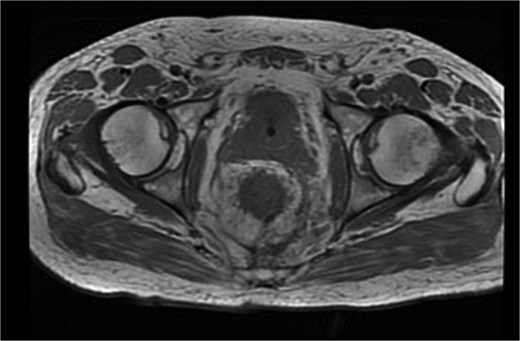

Histopathological analysis revealed a moderately differentiated adenocarcinoma. Colonoscopy showed no additional lesions and tumour markers were normal. PET-CT excluded distant disease. Pelvic MRI demonstrated involvement of the left levator ani, mesorectal fascia, and suspicious lymph nodes, suggestive of cT4bN1a disease (Fig. 4).

Final histology revealed a moderately differentiated tumour without nodal involvement or metastasis, suggesting that early perforation may have triggered bacterial dissemination and local necrosis without necessarily reflecting aggressive tumour biology. MRI findings of apparent invasion likely represented reactive inflammatory changes rather than true extension, consistent with final pathology.